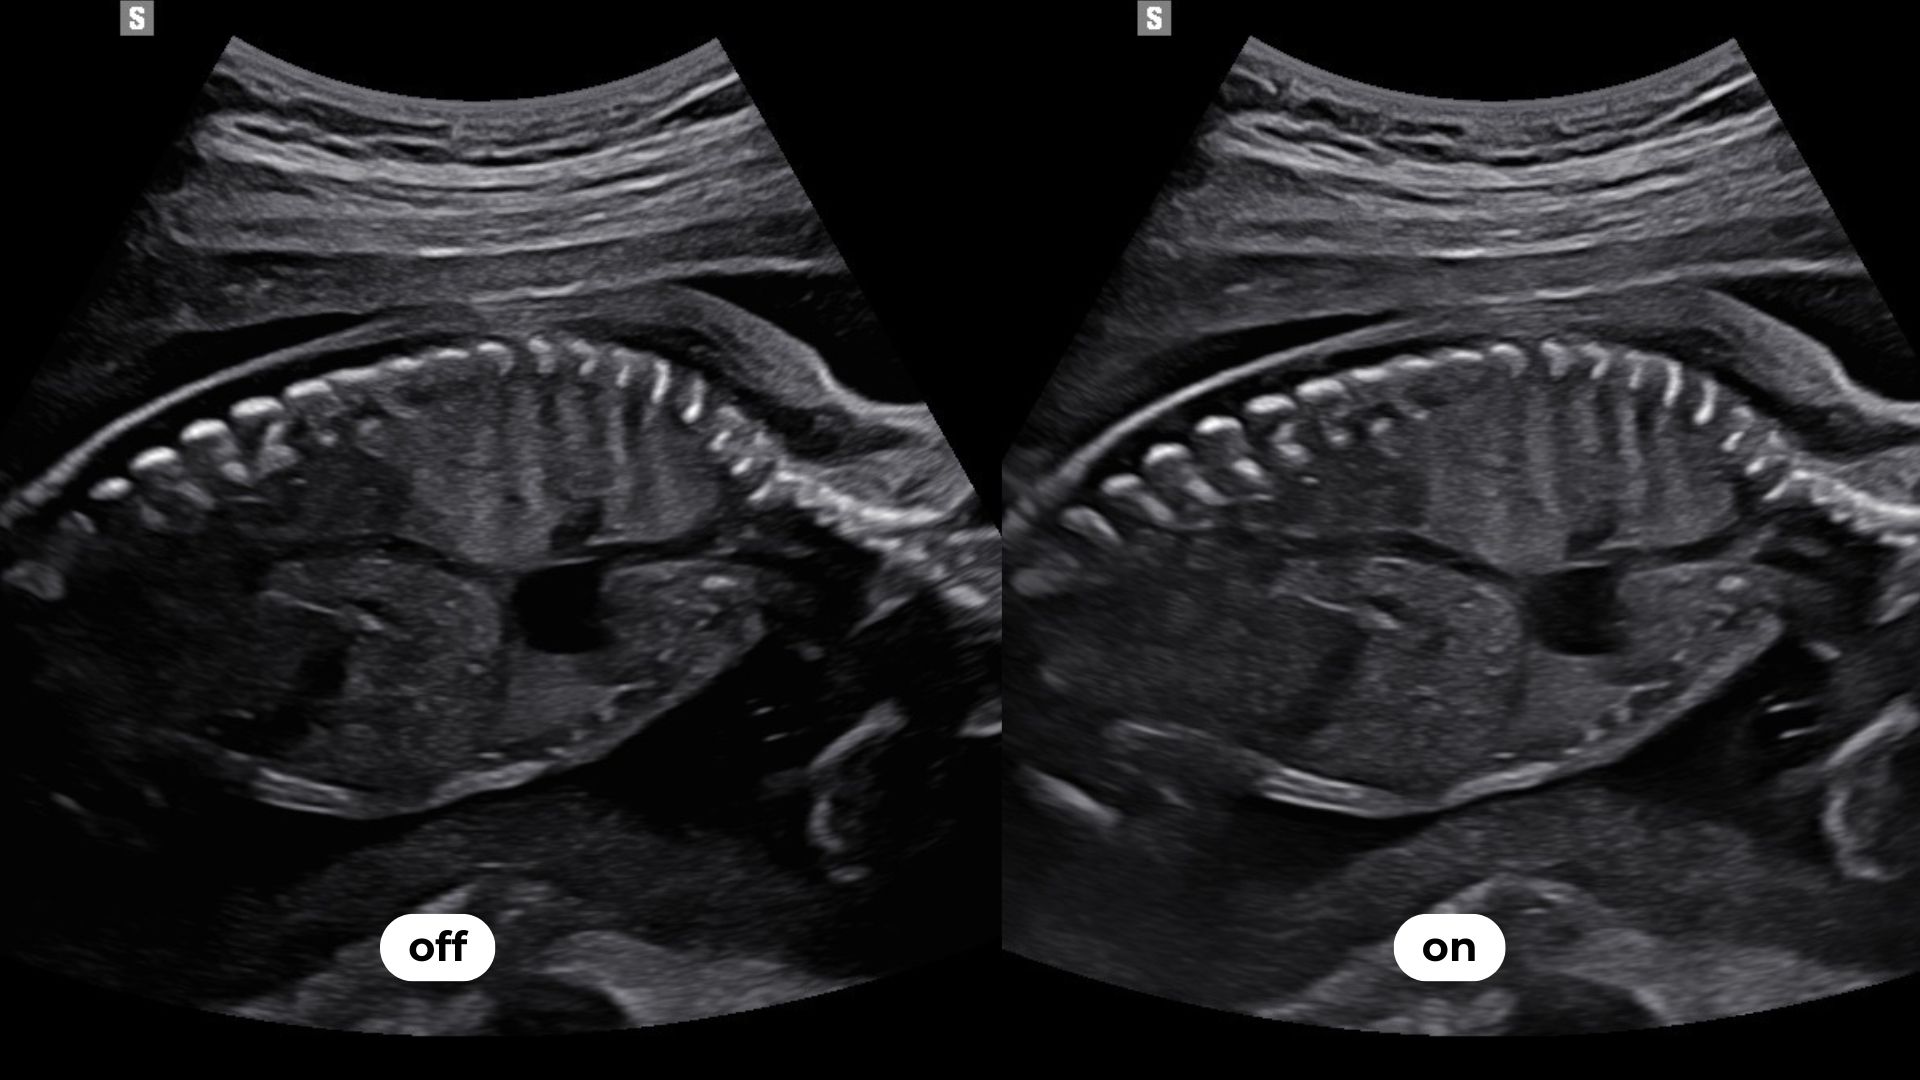

Luminant™ est un algorithme de différenciation structurelle qui transforme les contours d’une image 2D et améliore l’analyse des structures, comme pour le cœur ou le cerveau fœtal.

permet une sommation d’images réalisées sur des bandes de fréquences différentes et limite les surexpositions et atténuations du signal. Cet outil met en évidence des zones habituellement masquées comme les contours de la boîte crânienne.